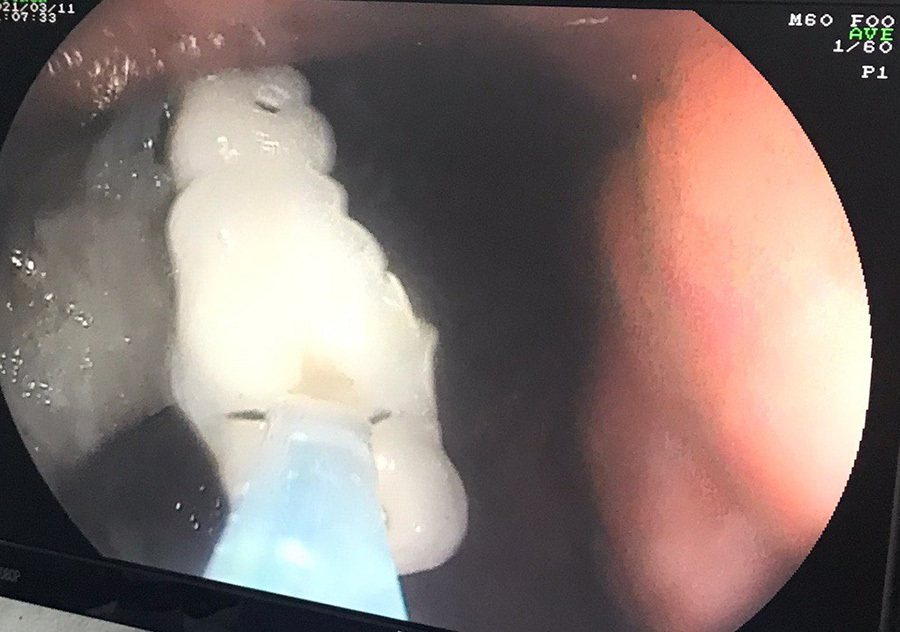

| Răng giả được lấy ra thành công |